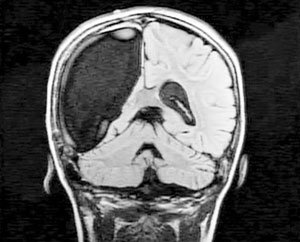

9-летняя жительница Бостона по имени Кэмерон поставила в тупик врачей и ученых. Всего за несколько недель, девочка смогла прийти в себя после сложнейшей операции по удалению правого полушария головного мозга.

Как сообщает eg.ru, начиная с трех лет Кэмерон, страдала тяжелой болезнью - синдромом Расмуссена или проще говоря, очаговым энцефалитом. Это коварная болезнь неизвестного происхождения начинается в детском возрасте и поражает только одно полушарие головного мозга, разрушая там нервные клетки.

В течение долгого времени малышку мучили судороги и тяжелые, едва ли не ежедневные, приступы эпилепсии. В конце концов, врачи вынуждены были удалить ребенку правое полушарие, которое отвечает за чувства, эмоции и ориентацию в пространстве.

Врачи честно предупредили родителей, что в результате девчушка может навсегда оказаться парализованной и остаться инвалидом. Но, к счастью, этого не произошло.

Кэмерон очень быстро пошла на поправку. Врачи не могут поверить, что выздоровление заняло так мало времени. Сегодня Камерон ничем не отличается от своих сверстников.